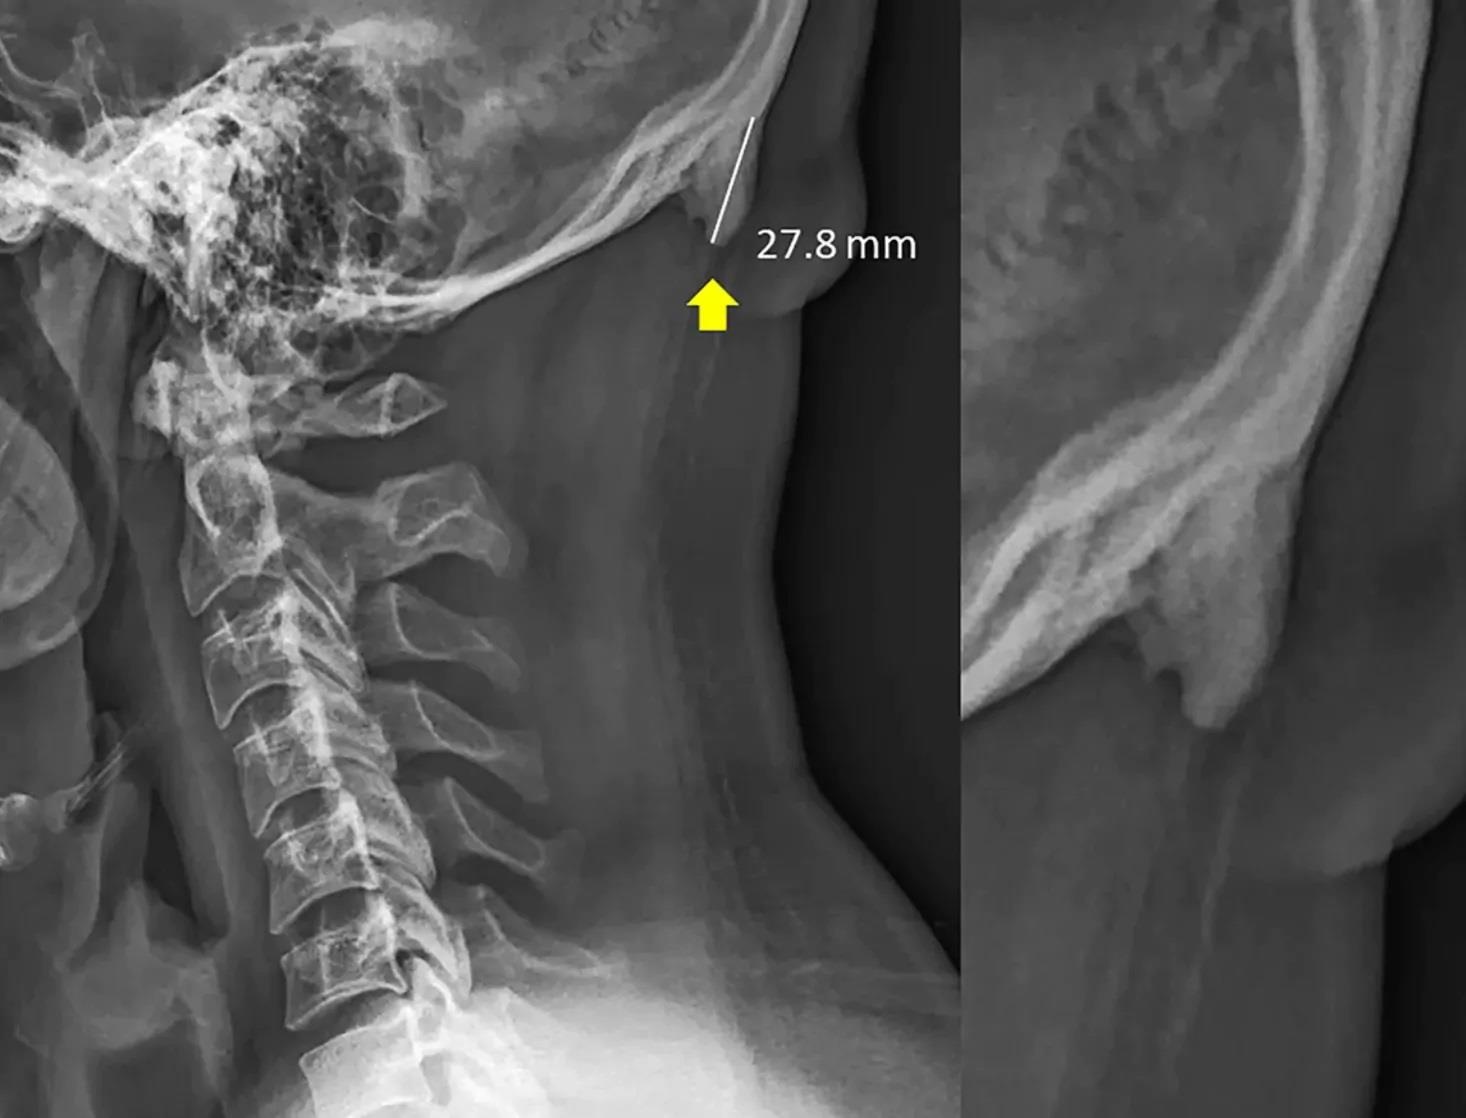

| Hình chụp X quang tại bang Queensland cho thấy một chiếc sừng nhỏ dài khoảng 2,8 cm mọc ra ở khu vực gân và dây chằng phía sau đầu, kết quả của quá trình vôi hóa mà nguyên nhân là do những gân và dây chằng này phải chịu quá nhiều áp lực. Ảnh: Scientific Report. |

Đề tài của hai nhà nghiên cứu bắt đầu từ 3 năm trước với một loạt những hình ảnh chụp X quang về vùng đầu và cổ của những đối tượng ở bang Queensland. Những hình ảnh cho thấy một phần của hộp sọ, bao gồm cả đáy gai nhô bên ngoài vùng chẩm (enthesophytes), được hình thành ở phía sau đầu.